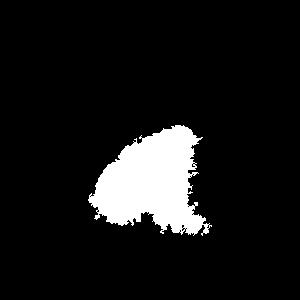

In order for the LDI scans to be comparable with BAM binary segmentations, a number of processing steps were conducted. LDI scans can have different sizes, scales, and cropping in comparison to their corresponding burn images. As BAM uses the burn 2D colour images as the input for creating the binary burn segmentations, the LDI scans were first aligned with their corresponding burn images and converted into the same size as those images. Once the LDI scans are aligned with input images and their colors are processed in order to create binary masks, quantitative comparisons with BAM segmentations were conducted. For this purpose, we utilised the manual segmentations of burn areas from burn images validated by clinicians.

Moreover, as discussed later, it was discovered that the LDI scan color palette, which demonstrates different healing potentials, would classify uninjured areas and background noise in the image as burns with poor blood flow. In a clinical setting, this misclassification does not lead to a serious issue as scans are reviewed by clinicians who can easily differentiate between normal skin/background and burn area. However, since the processing of LDI scans is conducted by computer vision, this issue needed to be resolved. This was addressed by removing the non-burn areas from the LDI scans before processing LDI scans by multiplying the aligned LDI scans with the manual segmentations of burn areas resulting in LDI scans that show various healing potentials (or various degrees of burn) in the burn area only.

4 Quantitative Analysis

We evaluated the performance of the BAM in segmenting burn areas from images using a dataset of manual segmentations validated by clinicians of burn areas from 2D colour images. We also compared BAM against Laser Doppler Imaging (LDI) results, the gold standard for assessing the depth and healing potential of burns. LDI generates a map of the blood flow in different parts of skin (including the burn areas) using laser Doppler technology. During scanning, laser light enters the skin tissue and is scattered by moving blood cells in the tissue. As a result, the frequency of the light changes according to the Doppler effect; the higher the speed and concentration of moving blood cells in a tissue, the higher the amplitude of the laser Doppler signal. This blood flow image is used to calculate three categories of healing potential for burn wounds; 1) less than 14 days, 2) 14 to 21 days, and 3) more than 21 days Med (2021)Hoeksema et al. (2009). The colors of a blood flow image and their corresponding healing potential categories are illustrated in Figure 6.